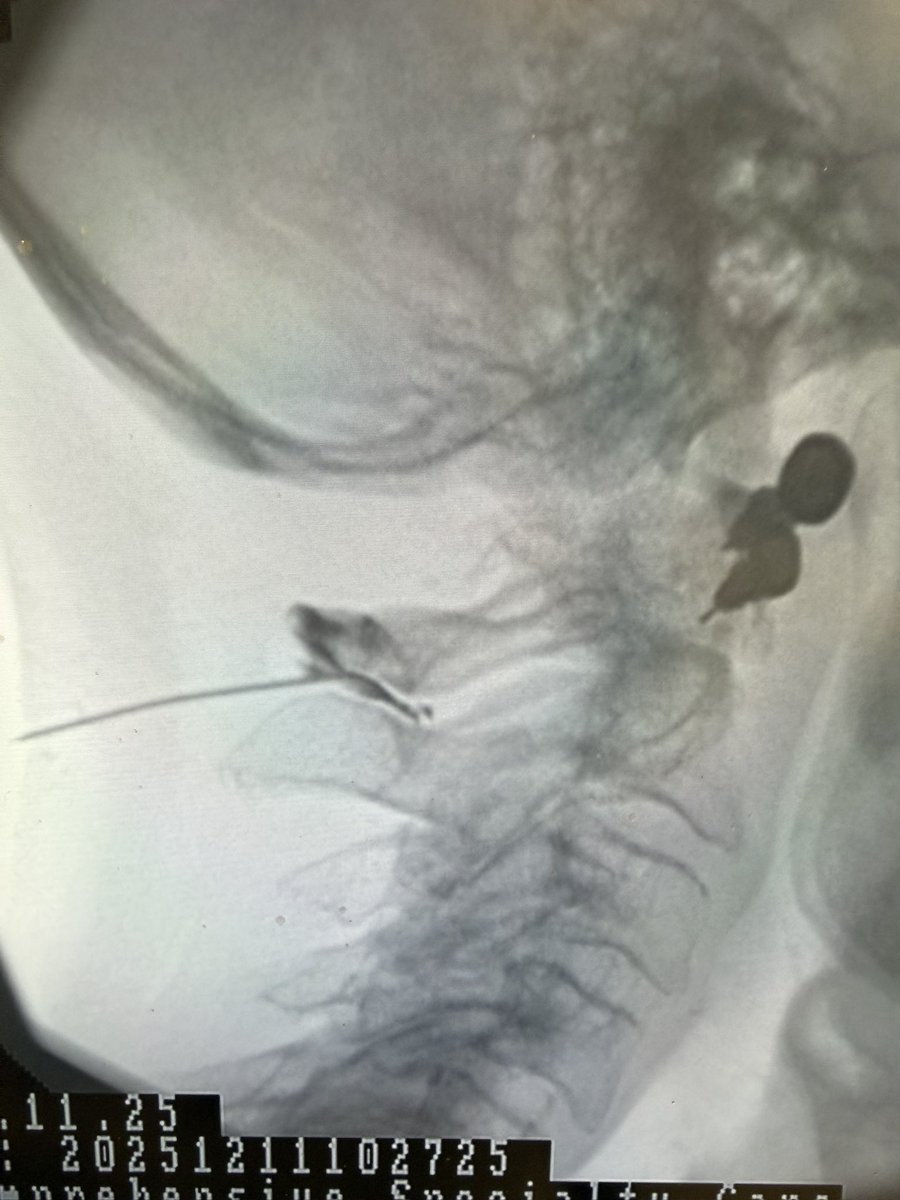

Interesting case of C1 – 2 interspinous bursitis treated with an injection of local anesthetic and steroid anti-inflammatory. Very effective treatment in this case.

Douglas Beall tweet mediaDouglas Beall tweet mediaDouglas Beall tweet media